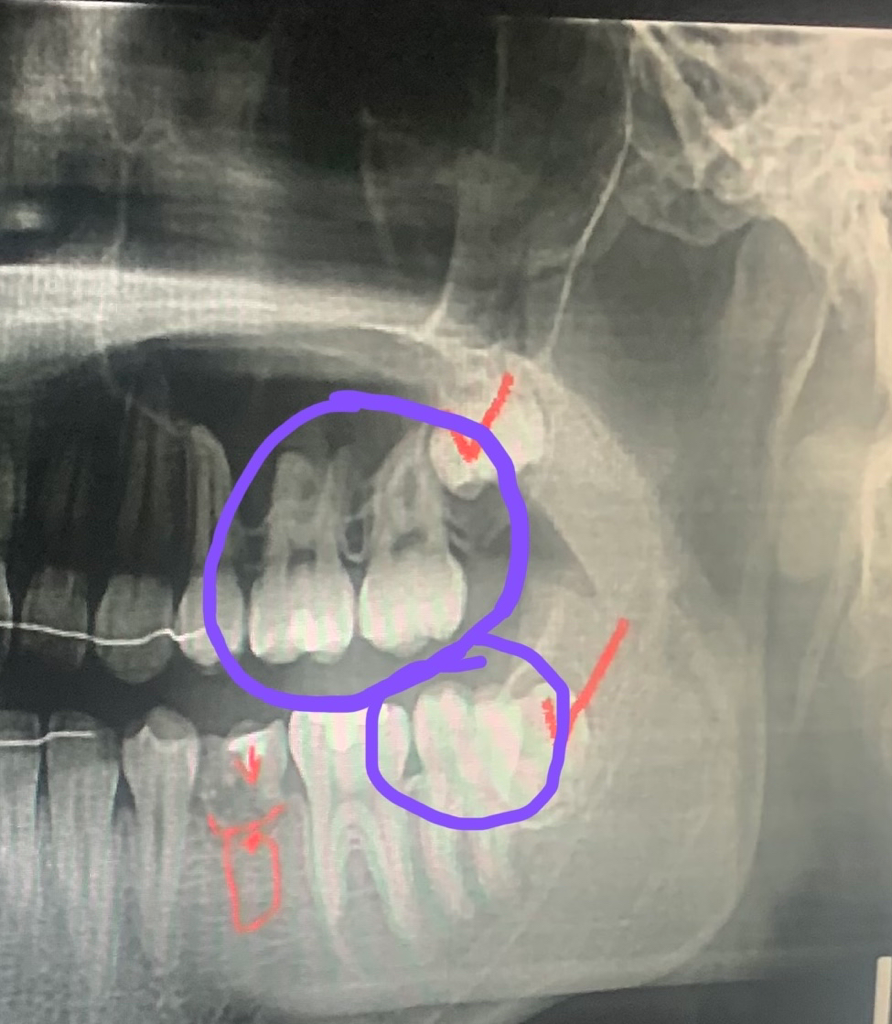

파란색으로 동그라미한 치아들은 인레이 치료해야한다고 의사선생님 께서 말씀 하시던데

솔직히 아래에 동그라미한 치아는 제가 봐도 인레이 치료해야 할것 같은데

혹시 위에 치아 두개도 꼭 인레이 치료 해야할까용??

방사선 사진으로는 충치가 크게 보이거나 하지는 않습니다.

치아의 표면에 충치가 생긴것으로 생각됩니다 충치의 범위가 치아의 인접면에 생겼거나 전체 크기의 1/3 이상이라면 인레이 치료를 하는 경우가 많습니다.

정확한건 엑스레이도 중요하지만, 실제 구강내 사진을 봐야 정확히 알수 잇을것같습니다. 위쪽 예전에 치료하신 치아도 범위가 넓어보이긴 하나 그게 충치인지는 구강내에서 직접봐야 알수 잇을것같습니다.